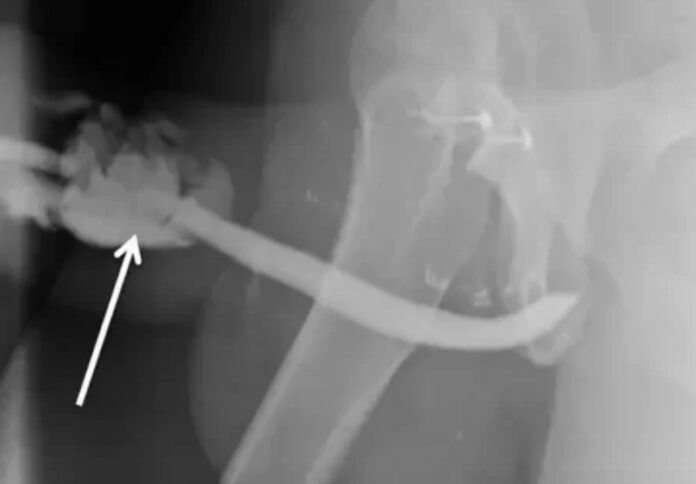

Um morador da Tanzania de 36 anos, teve uma rara fratura em três lugares diferentes do pênis durante o sexo. O caso ocorreu enquanto ele fazia uma das posições sexuais mais propensas a ocorrerem lesões deste tipo.

Como morava em uma cidade pequena, o homem teve que esperar cinco horas desde o acidente até o atendimento médico. No posto de saúde de sua comunidade, ele recebeu apenas analgésicos. Enquanto isso, o pênis fratura chegava a gotejar sangue.

O tanzaniano teve de passar por uma cirurgia de emergência no hospital de Kilimanjaro para que o órgão fosse reconstruído, já que o órgão torcido e em um formato que os médicos descreveram como semelhante a um balão. Depois do procedimento e do período de recuperação, o pênis do paciente voltou a funcionar normalmente.